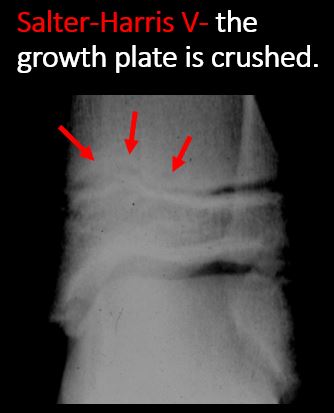

There is narrowing of the physis from a compression fracture (S-H V). [Yes/No]